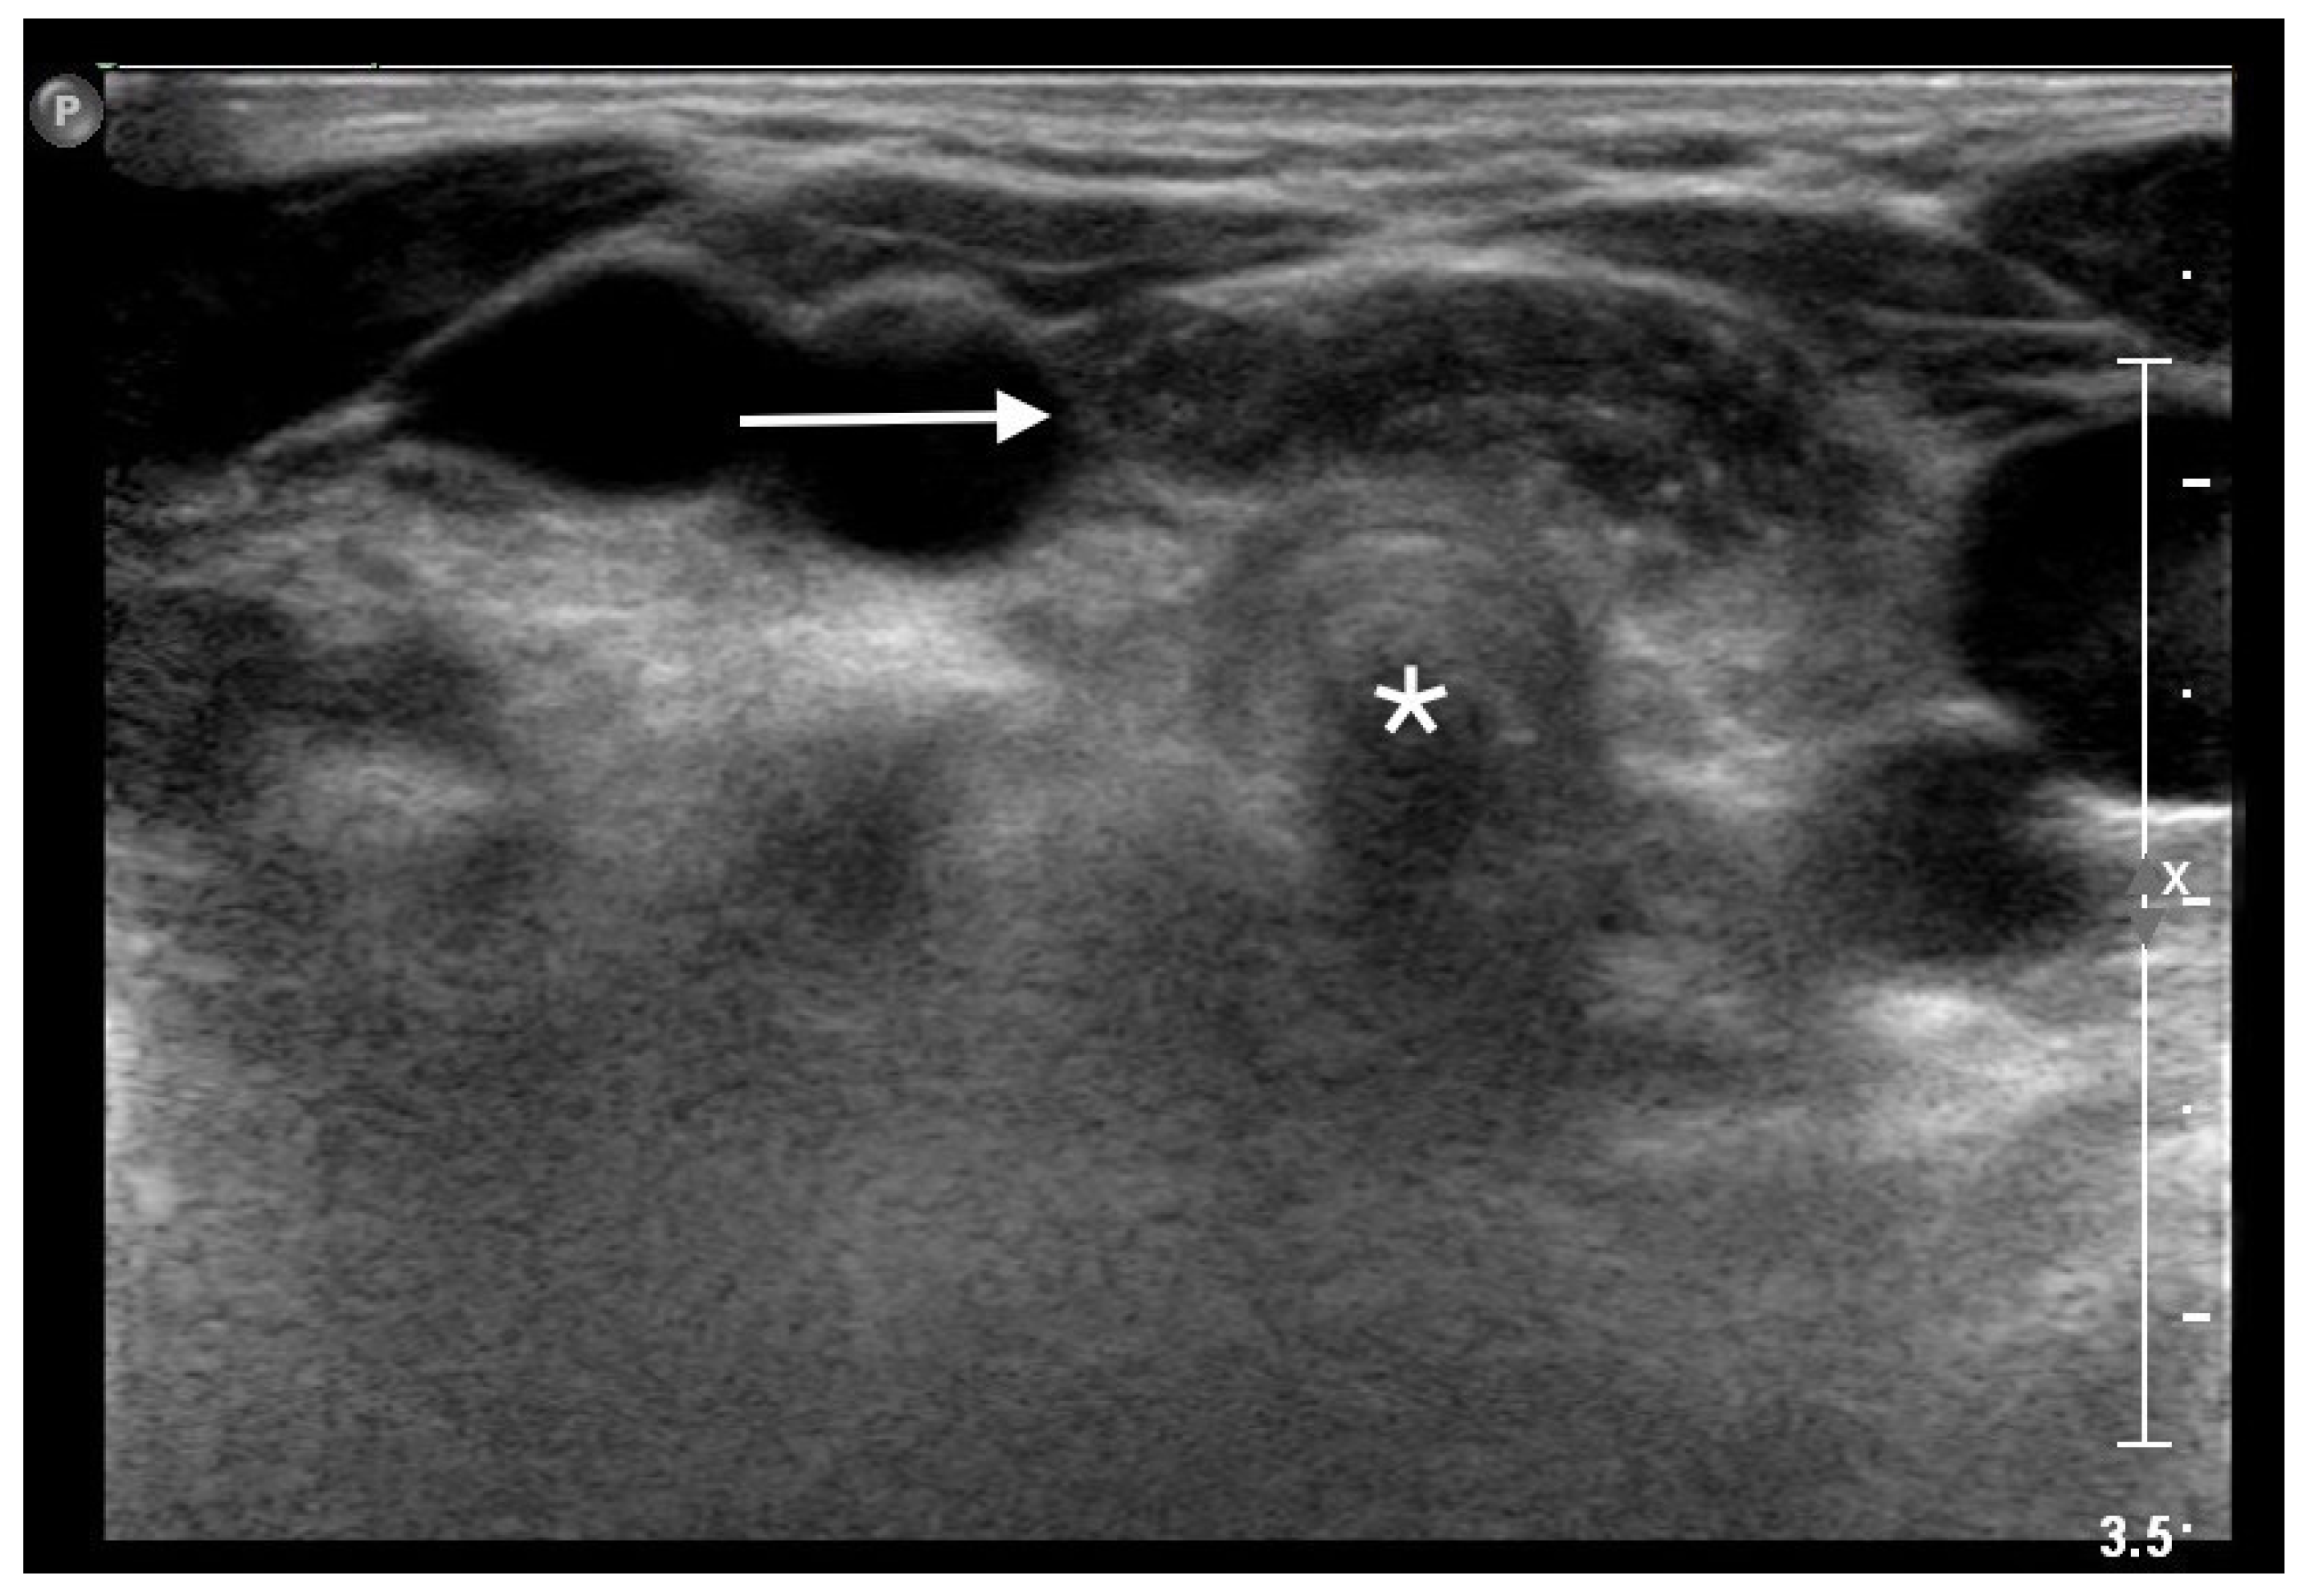

An MRI of the neck, carried out under general anesthesia, showed an orthotopic thymus, located into the anterior mediastinum, without any mass effect. After the MRI, a dynamic ultrasonography was carried out during the Valsalva maneuver, showing the superior herniation of a mass with the sonographic appearance of the normal thymus. The mass consisted of a roughly oval structure, with multiple linear hyperechoic septa, and scattered hyperechoic foci, giving a characteristic “speckled” or “starry sky” appearance. The ultrasound examination showed the intermittent superior movement of the thymus into the cervical region, reaching the cervical trachea, without any buckling or displacement of adjacent structures (Figure 1).

Superior herniation of the normal mediastinal thymus in a 5-year-old girl. Transverse sonogram obtained during the Valsalva maneuver showing a roughly oval structure (white arrow) with the typical “starry sky” appearance of thymus, in front of the cervical trachea (white star).